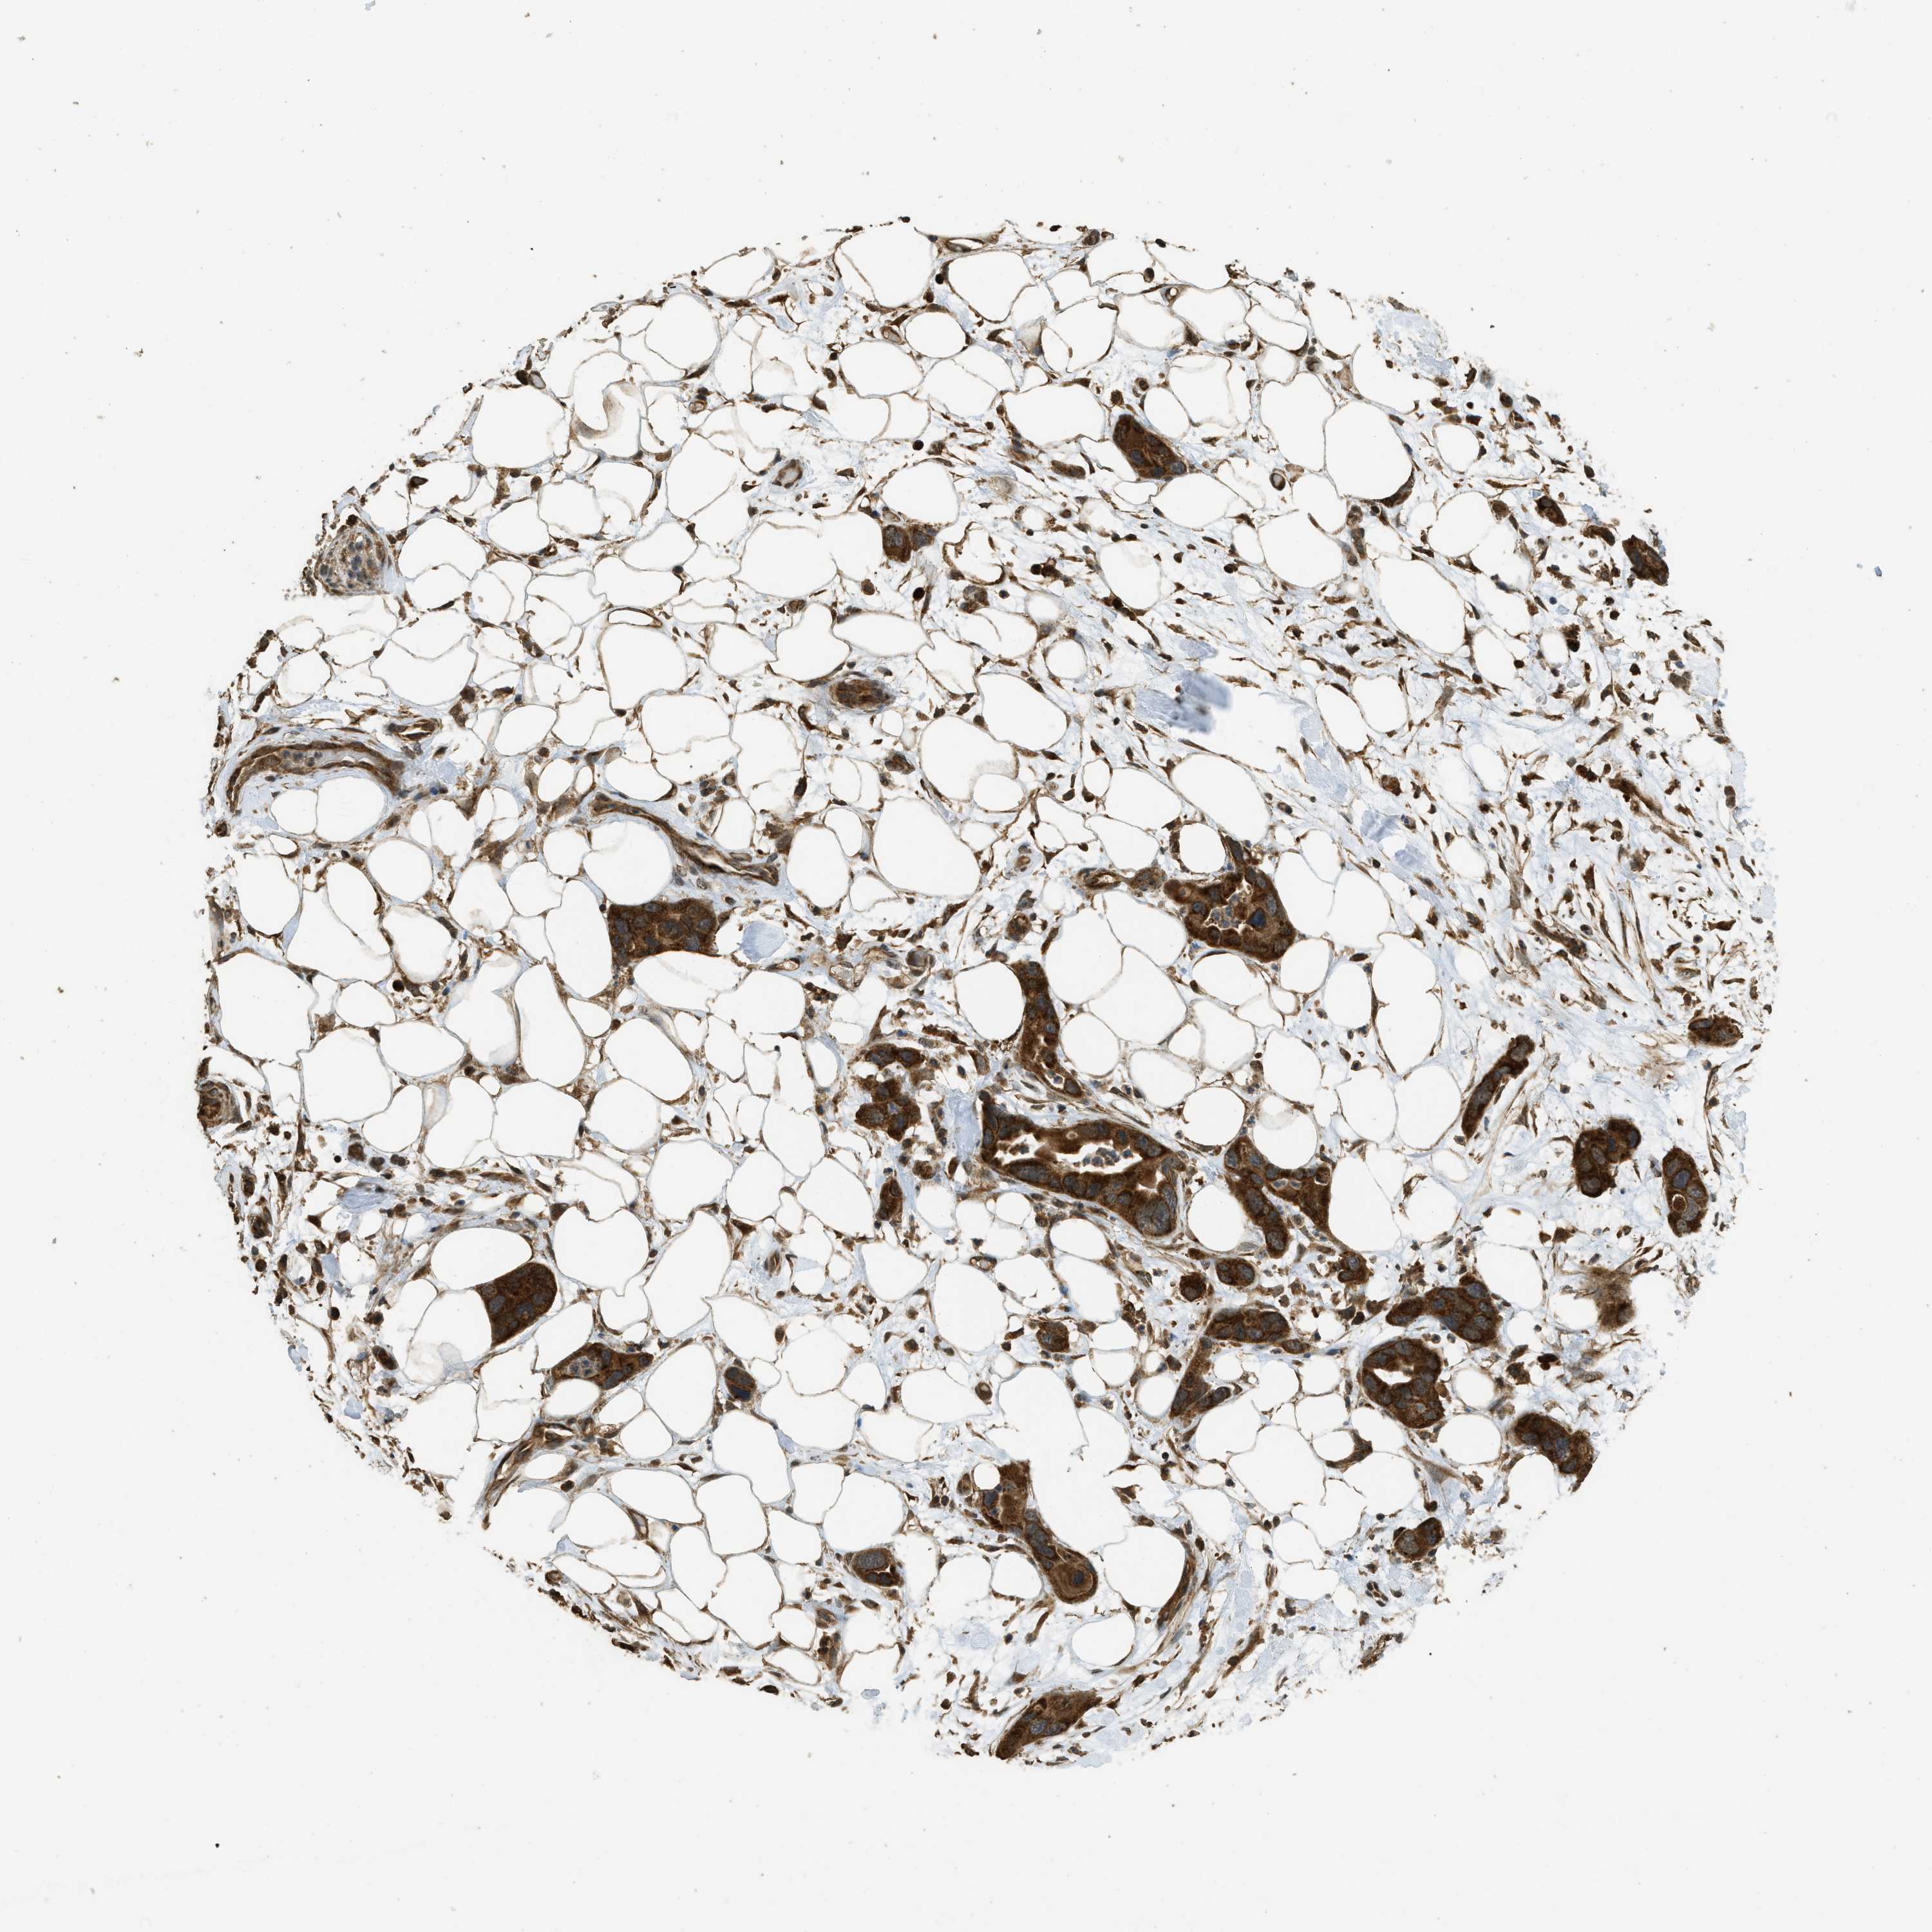

PANCREATIC CANCER - Protein expressioni

A mouse-over function shows sample information and annotation data. Click on an image to view it in a full screen mode. Samples can be filtered based on level of antibody staining by selecting one or several of the following categories: high, medium, low and not detected. The assay and annotation is described here.

Note that samples used for immunohistochemistry by the Human Protein Atlas do not correspond to samples in the TCGA dataset.

Antibody stainingi

Antibody staining in the annotated cell types in the current human tissue is reported as not detected, low, medium, or high, based on conventional immunohistochemistry profiling in selected tissues. This score is based on the combination of the staining intensity and fraction of stained cells.

Each image is clickable and will lead to virtual microscopy that enables deeper exploration of all samples and also displays staining intensity scores, fraction scores and subcellular localization as well as patient and tissue information for each sample.

Antibody HPA051322

Antibody CAB017111

Staining

High

Medium

Low

Not detected

Intensity

Strong

Moderate

Weak

Negative

Quantity

>75%

75%-25%

<25%

None

Location

Nuclear

Cytoplasmic/membranous

Cytoplasmic/membranous,nuclear

Adenocarcinoma, NOS